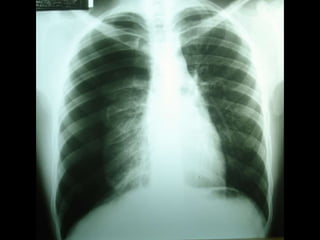

• Diagnóstico – Anamnese –Exame físico – Radiografia de tórax • Inspiração profunda (A) • Expiração profunda – TC de tórax